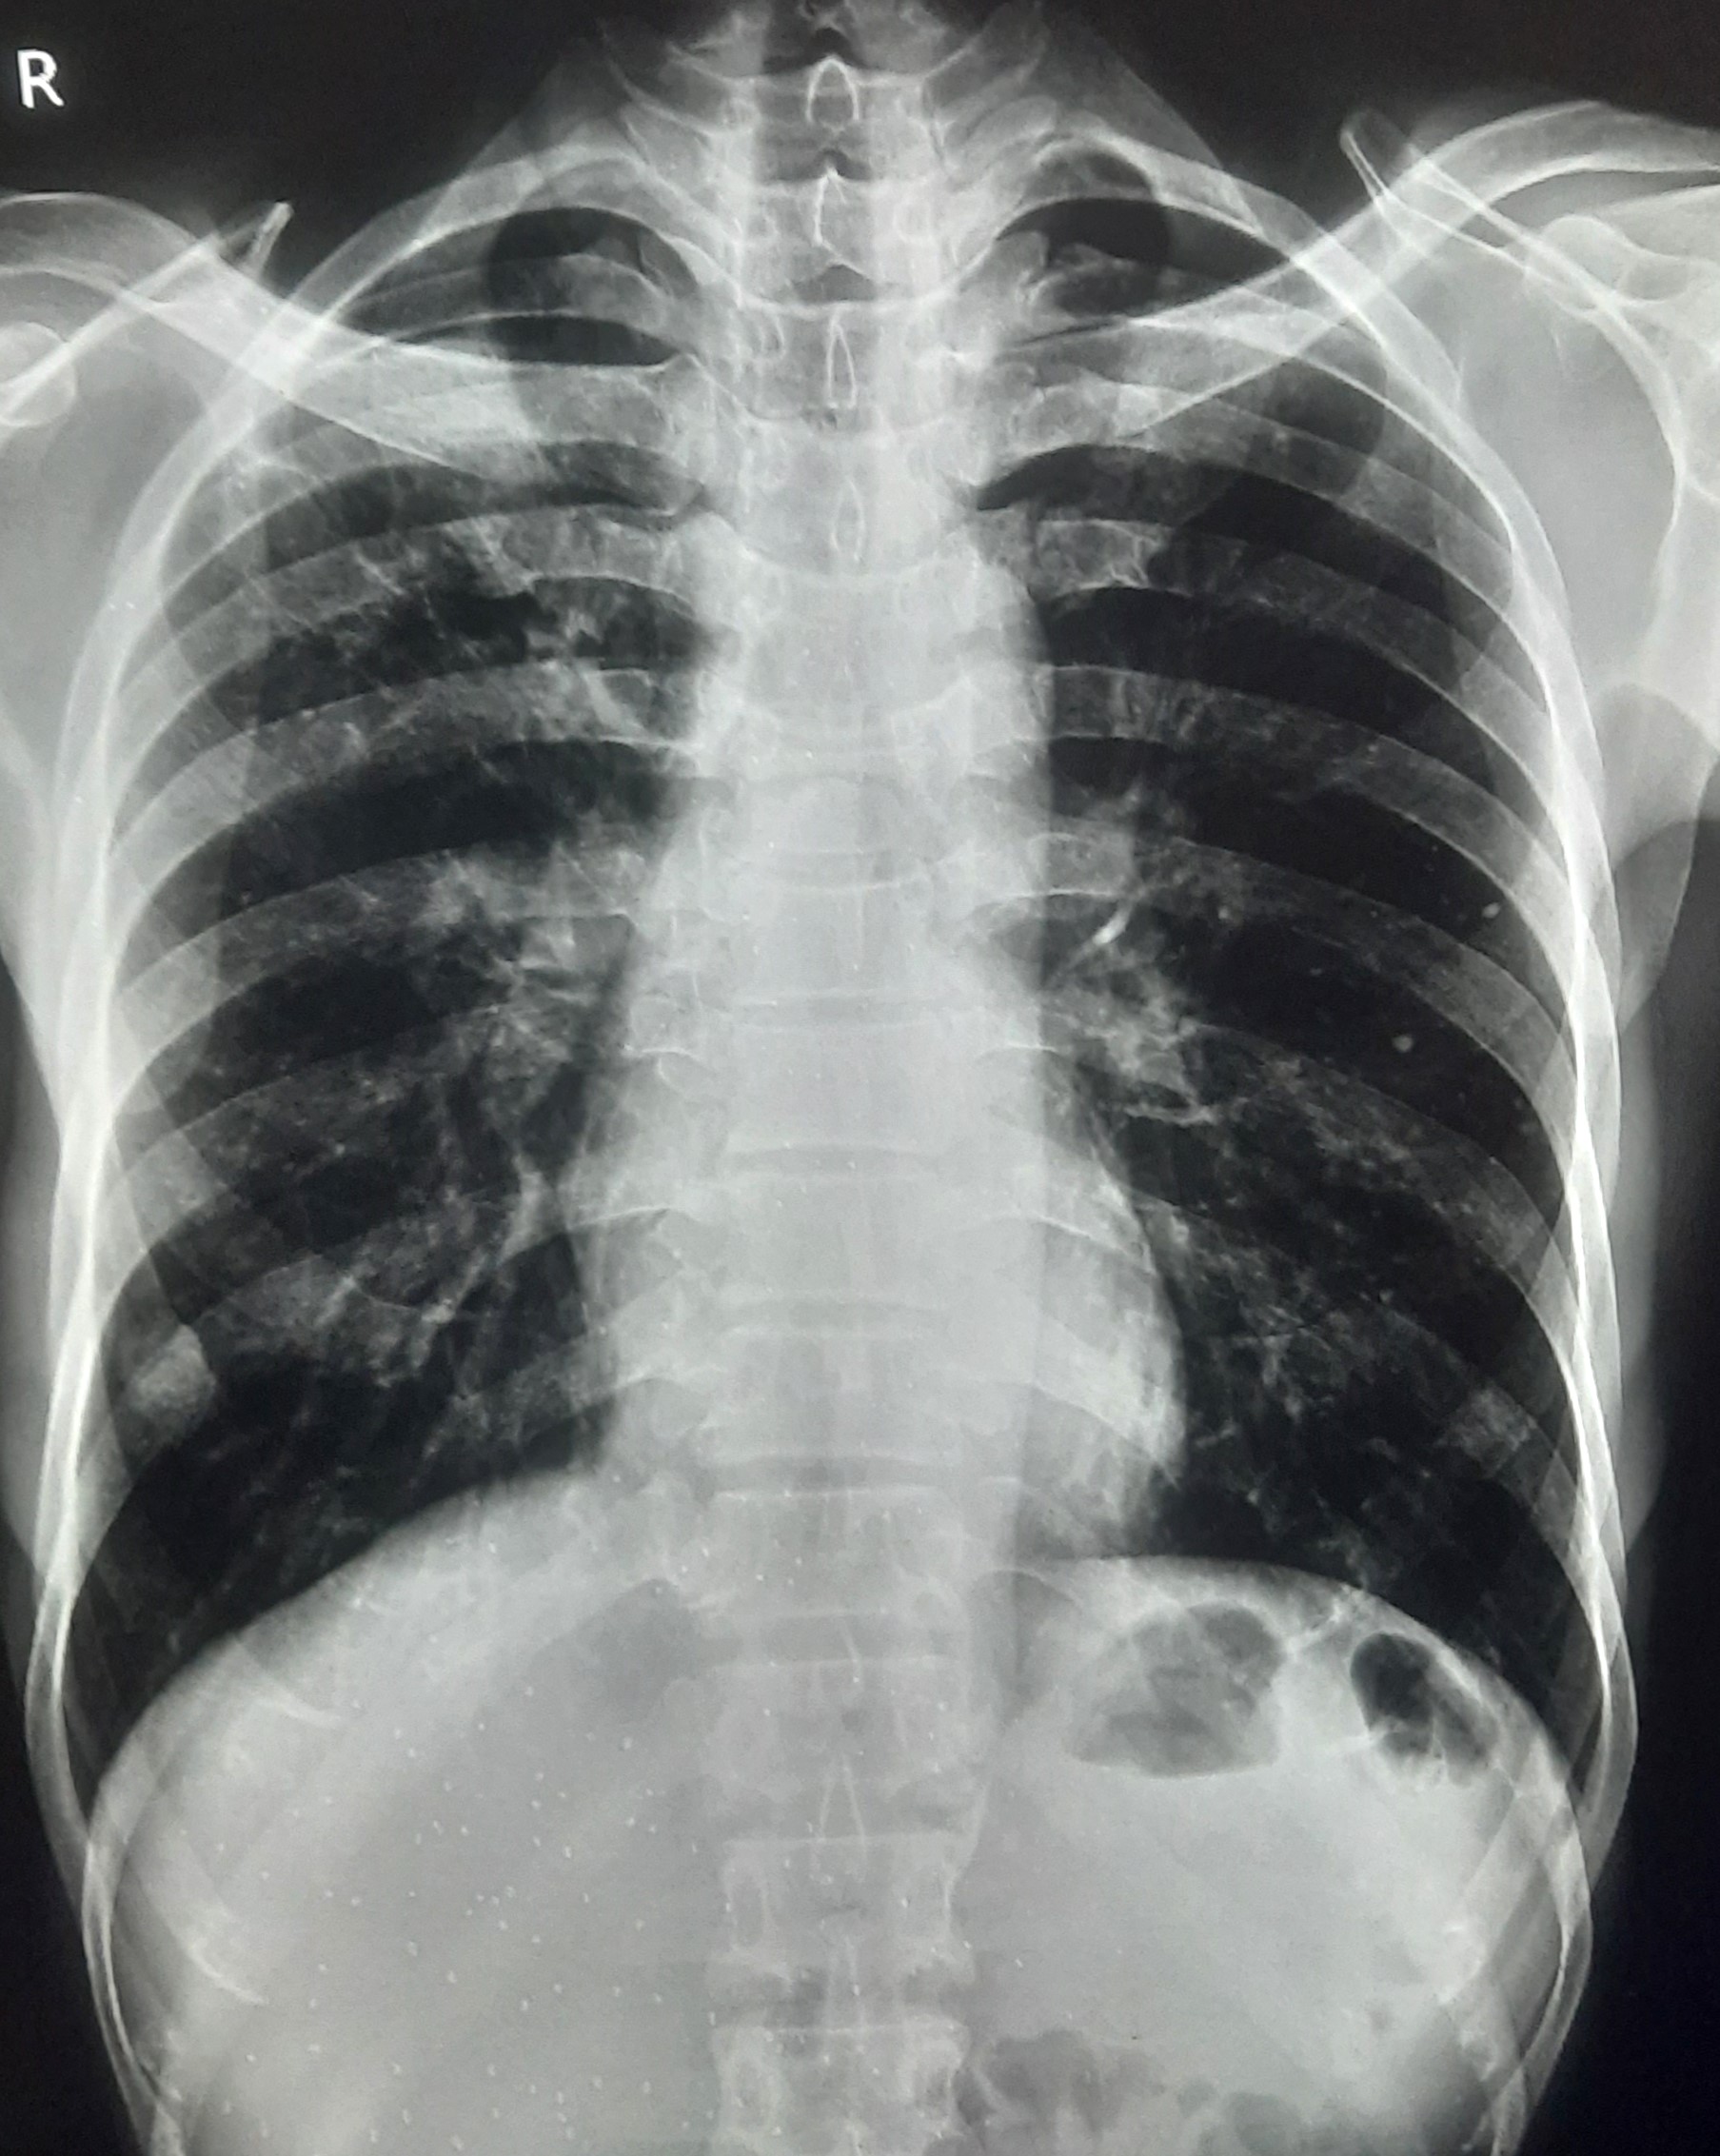

| 283 | IGGMC, Nagpur, Nagpur | P2 | 29-4189 Follow-up of 29-3923 |

Monali Pralhad Milmile | Consent taken on Paper | 46 Yrs. |

Provisional Diag : PTB Follow-up

Final Diag : Pleural Effusion |

TB Case (Confirmed) | Right Sided Upper Zone Fibrotic Lesion, Tracheal Pull Left side, Right sided & Left Sided Pleural Thickening Present, Right sided & Left Sided CP Angle Blunting Present, | Abnormality visible on x-ray |